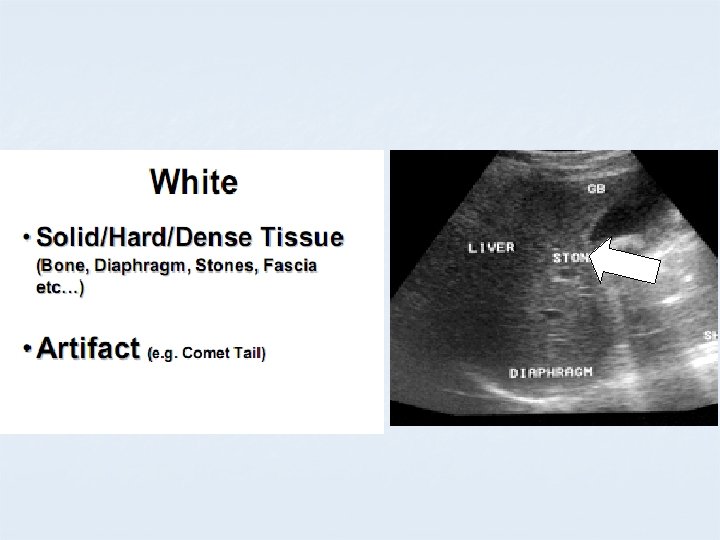

B MODE COLOURS BLACK ANECHOIC GREY HYPOECHOIC WHITE ECHOGENIC

APPEARANCE OF DIFFERENT TISSUES STRUCTURE APPEARANCE Viscera ; Liver Spleen Hypoechoic Muscles Hypoechoic with echogenic lines Blood, Urine, Bile, ascites, water Anechoic Bone, Stone Hyperechoic